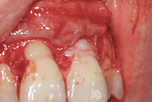

Posizionamento di un innesto di tessuto connettivo prelevato dal palato.